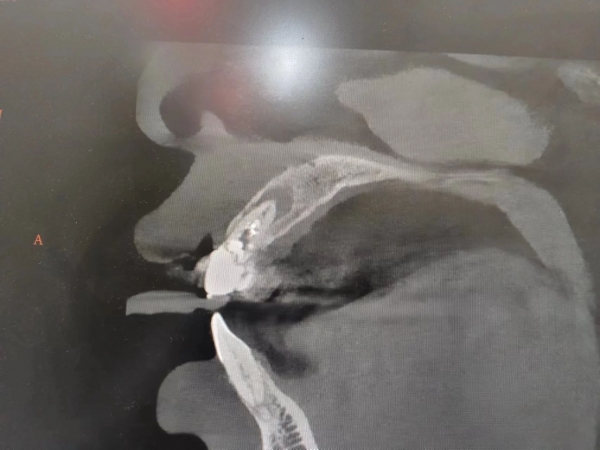

鄭州西區(qū)中醫(yī)院口腔科主任李明濤介紹,由于兒童正處在身體、生理、心理生長(zhǎng)發(fā)育階段,心智發(fā)育尚不健全,較成人更易發(fā)生外傷事故。特別是學(xué)齡時(shí)期的兒童,在劇烈的運(yùn)動(dòng)或玩耍時(shí)易發(fā)生碰撞、跌倒,有時(shí)會(huì)造成牙外傷。

當(dāng)牙齒受傷害后無明顯變化,應(yīng)當(dāng)盡早到醫(yī)院進(jìn)行檢查,由口腔醫(yī)生來判斷受傷牙齒的具體情況,進(jìn)行規(guī)范治療處理。

發(fā)現(xiàn)孩子受傷牙齒折斷,可以保留折斷的牙片,流水沖洗干凈后浸泡在清水中。折斷的牙片切勿丟棄,盡快找就近的醫(yī)院,讓口腔醫(yī)生進(jìn)行處理。醫(yī)生會(huì)根據(jù)牙外傷和面部損傷的情況采取不同的應(yīng)急處理。

如果是新萌出的年輕恒牙完全脫出,牙齒復(fù)位到牙槽窩的時(shí)間及脫位牙齒的保存方式對(duì)外傷牙的預(yù)后非常重要。應(yīng)盡快找到脫落的牙齒,用手捏住牙齒的牙冠部分用流動(dòng)水沖洗掉牙齒表面的臟東西。不要用手去觸碰牙根,將清潔的外傷牙盡量放回牙槽窩。